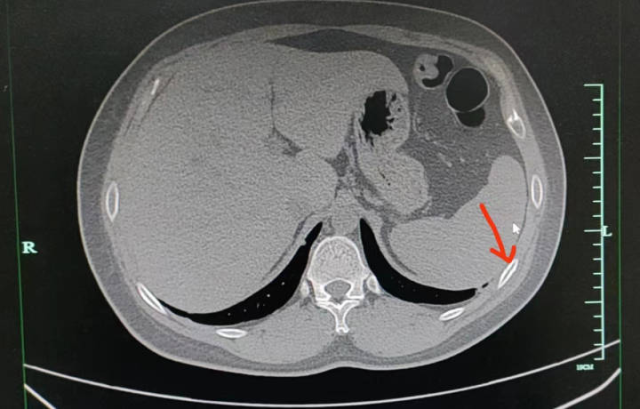

医生注意到,正常状态下,聂先生胸口只有轻微痛感,但在咳嗽或按压时,疼痛会明显加重。经过进一步的CT检查发现,聂先生右侧第五、第六肋骨都骨折了。

162646dltpj3thl9dzardp.png

医生解释,肋骨骨折与其他骨折不同,它不承受重量,所以在静息状态下通常没有疼痛感。但当肋骨受到外力按压或胸廓活动较大时,如咳嗽或深呼吸,就会引发疼痛。

“咳断肋骨的情况在骨质疏松的老年患者中较为常见。像聂先生这样年轻、体型正常、营养均衡的患者是较少见的案例,可能是由于咳嗽时间持续过久,造成了肋骨部位反复受到牵拉而引发的疲劳骨折。”医生表示。